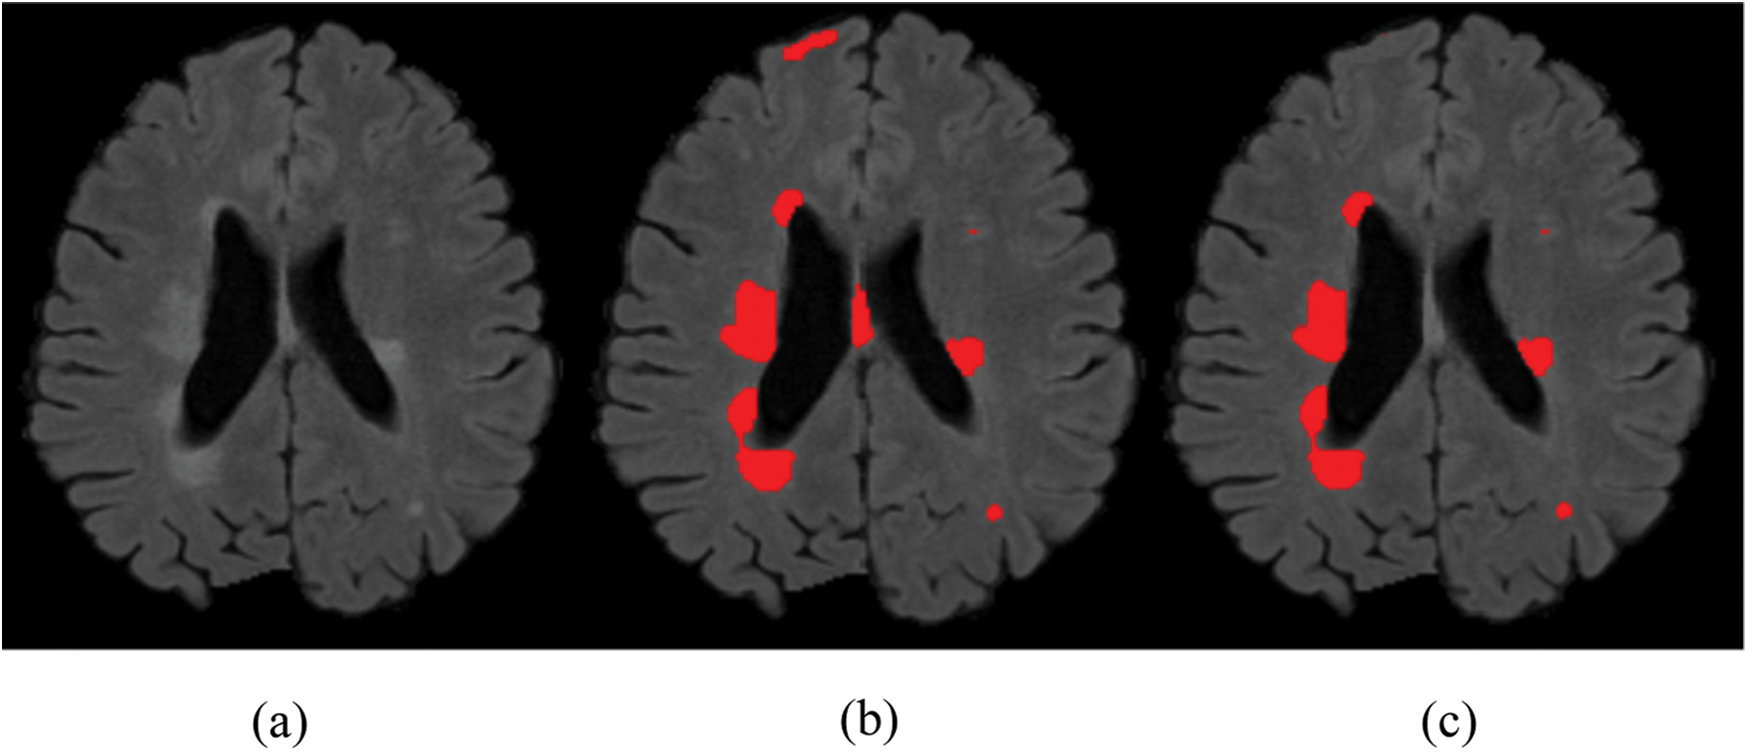

and received good results as mentioned in the evaluation Section 4. Also, 3 modalities T1-w, T-2 w, and FLAIR are taken as input. The reason for taking 3 modalities is that, FLAIR is mainly used for segmentation purposes whereas the other 2 modalities T1-w and T2-w are used to reduce artifacts and help us to reduce false positives which are mentioned in Fig. 4. The comparison of one modality versus three modalities is shown in Fig. 5. The results show that when three modalities are used, MRI artifacts can be reduced greatly. The exact implementation details are discussed in Section 4.1.

Figure 5: Comparison between 1 modality and 3 modalities. (a) Original image. (b) 1 modality. (c) 3 modalities